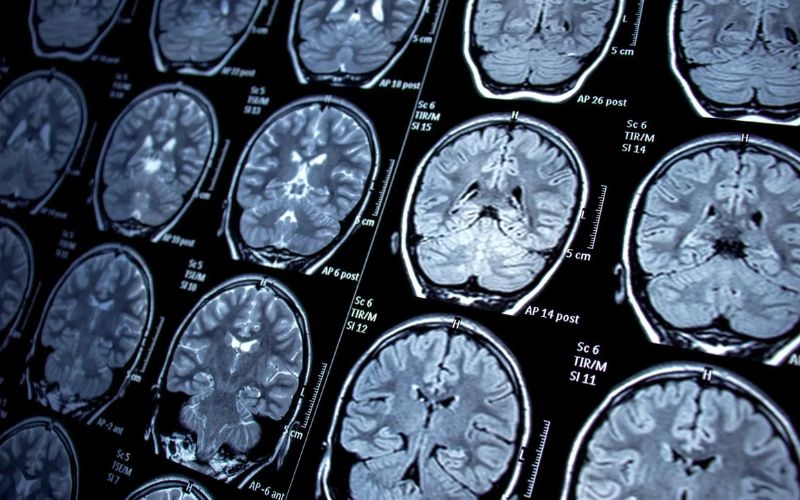

- Chụp CT hoặc MRI mạch máu: Cung cấp hình ảnh chi tiết về thành mạch và mảng xơ vữa. Đặc biệt hữu ích trong đánh giá mạch vành, động mạch cảnh, động mạch chủ.